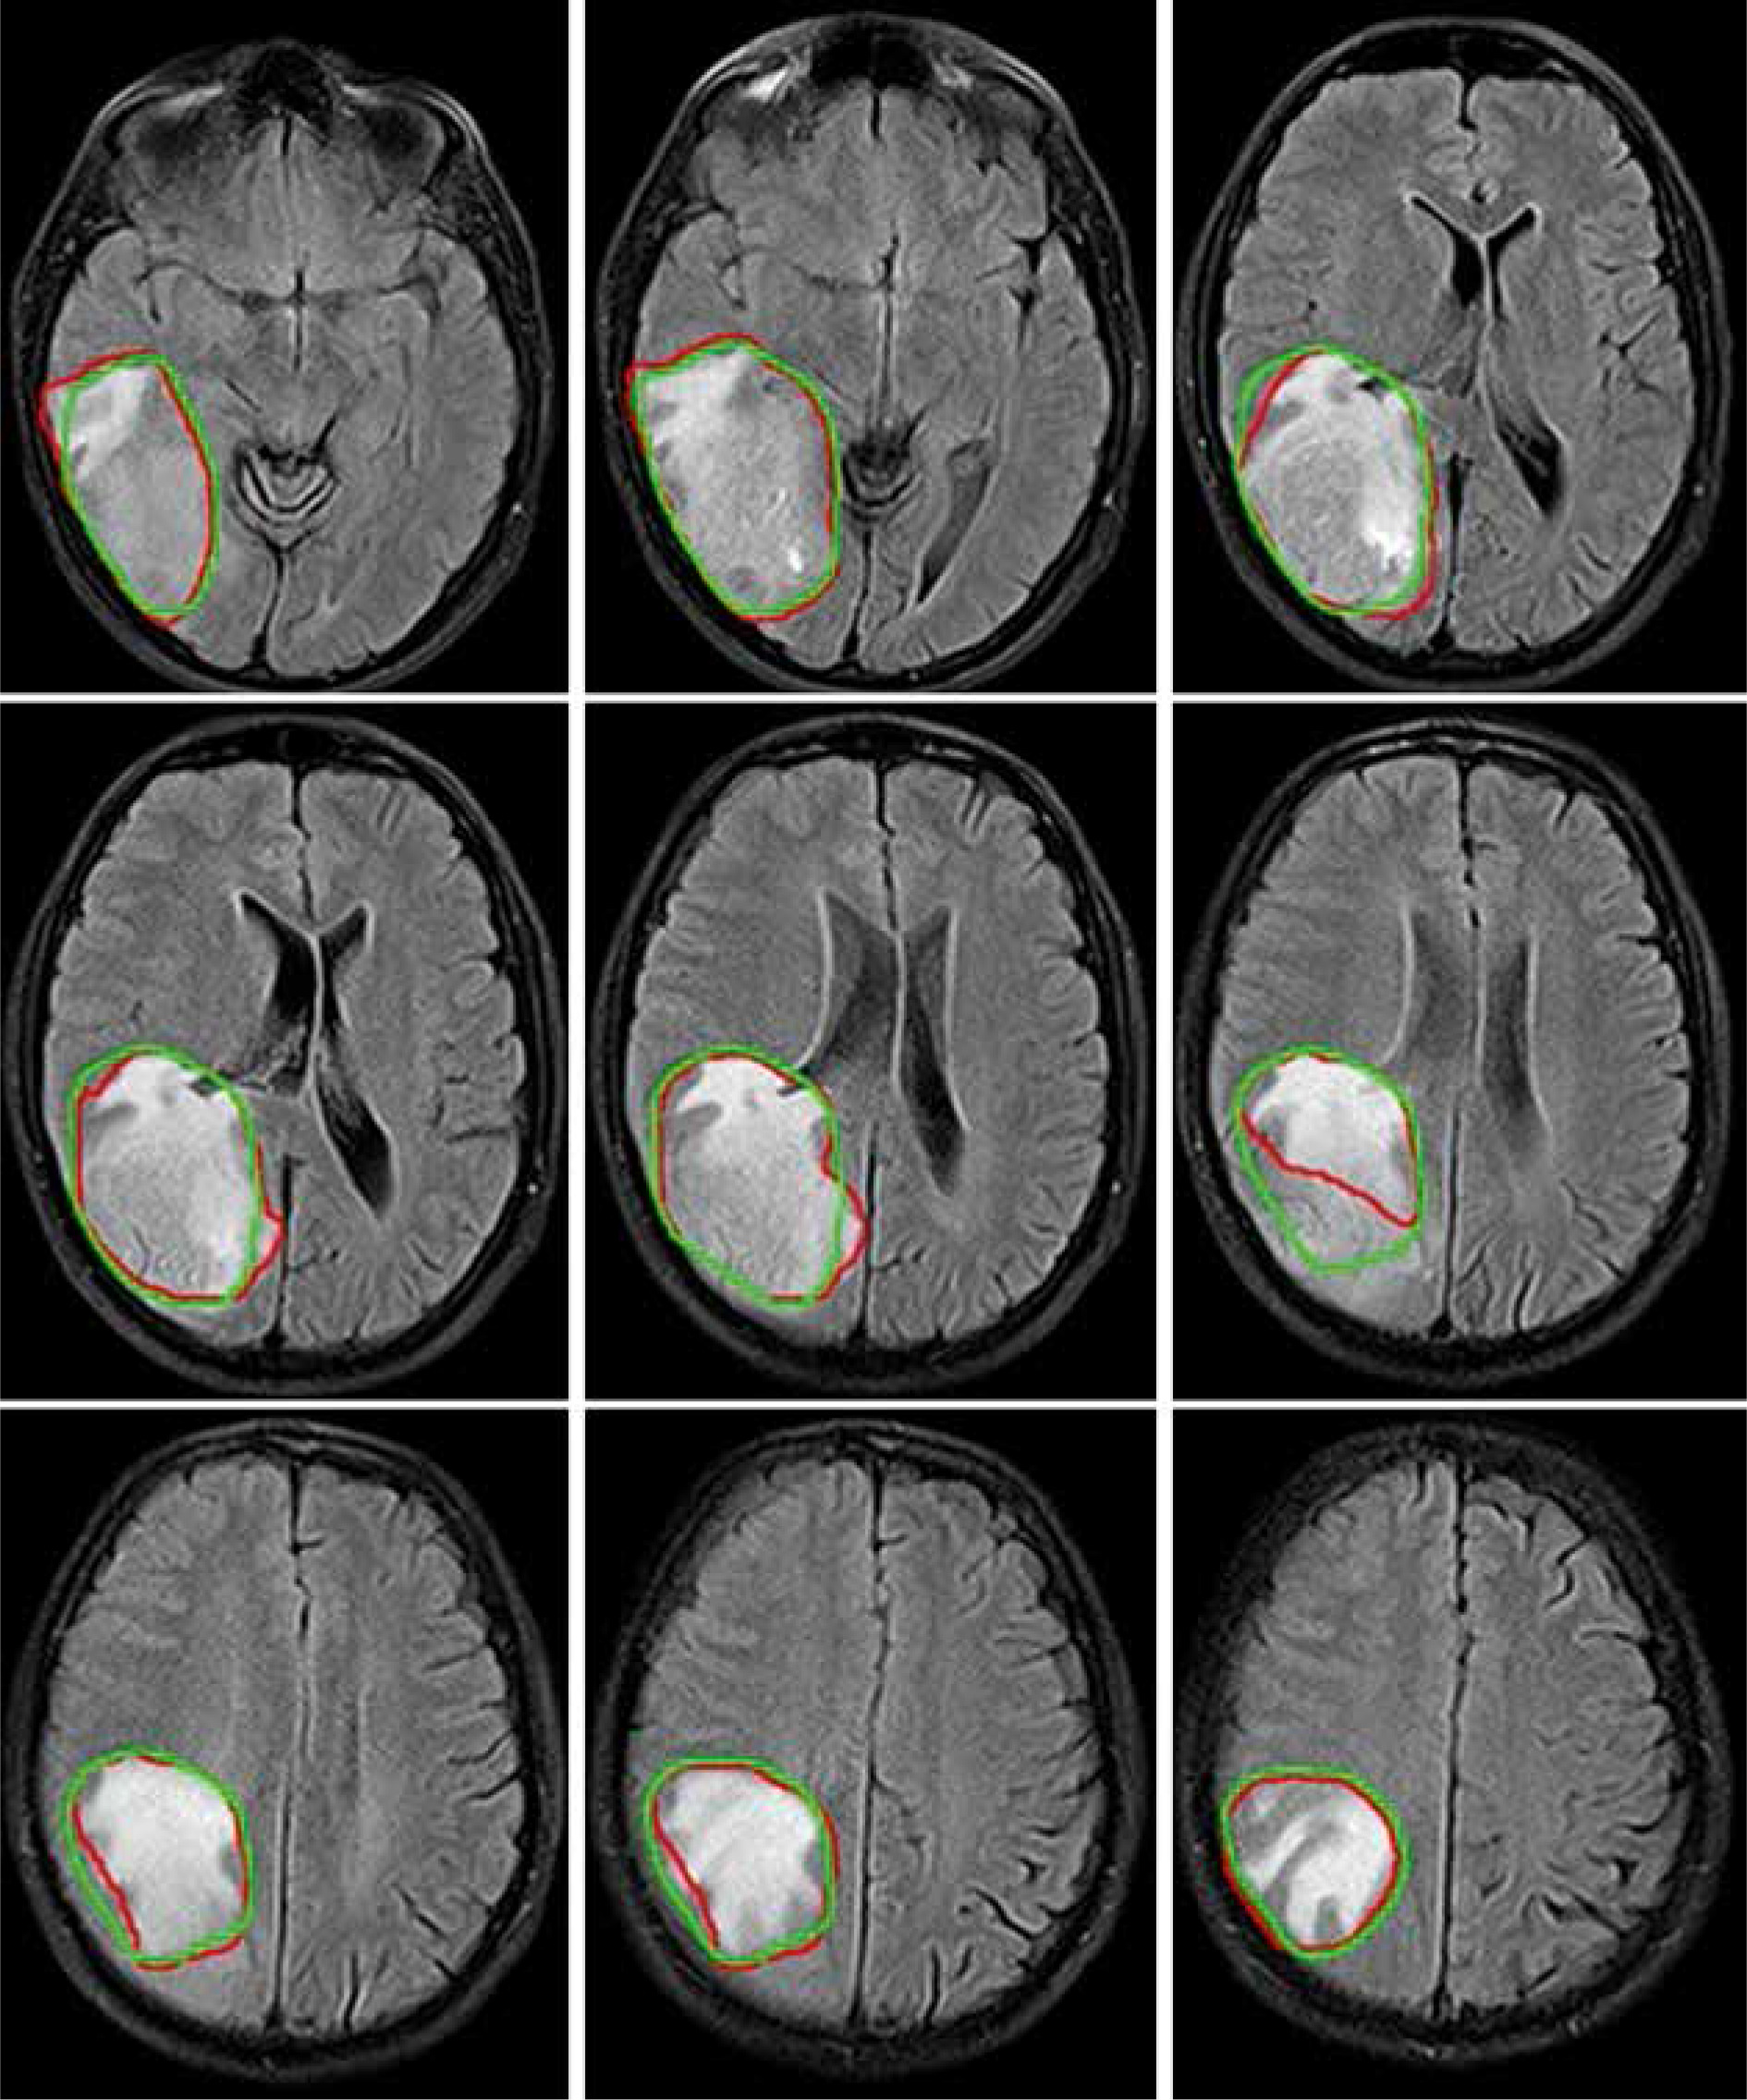

Figure 3 illustrates a comparison of manual versus automatic segmentation of CTV for 15 glioblastoma patients which used as the testing dataset in this study. As shown in Figure 3, most deep learning-based auto-segmented volumes are smaller than the expert radiation oncologist volumes. The mean ± standard deviation (SD) CTV volumes segmented manually and by the modified SegNet model were statistically significantly different: 73.5 ± 48.3 cc and 63.0 ± 38.2 cc, respectively (p = 0.004). Axial T1w MRI images of a representative case with manually and automatically delineated contours of the CTV on the external testing dataset are shown in Figure 4. Also, Figure 5 presents the CTV volumes of automatic and expert segmentations as the ground truth on the different views of CT images of 3 patients chosen randomly from the external testing dataset (n = 15).

Figure 4

Examples of automatically generated contours (red) vs. ground truth (green) on axial view of T1cw magnetic resonance images of a representative case